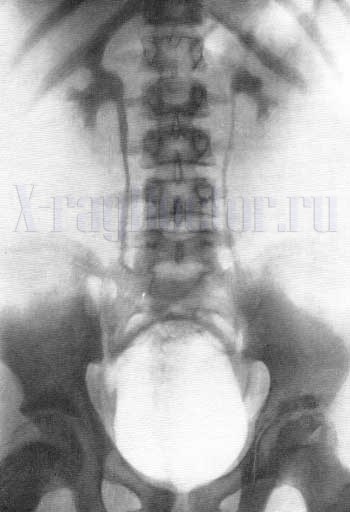

Что показывает обзорная урограмма

Обзорная урография проводится без контраста. При ней делают снимок области расположения органов мочевыделительной системы. Снимок показывает следующие патологические состояния:

- камни лоханки и уретры;

- опущение или смещение почки;

- удвоение или гипоплазию (недоразвитие) почек;

- аномальное строение мочевого пузыря;

- атипичный ход мочевыделительного канала.

Обзорный снимок также позволяет исключить наличие свободного газа в брюшной полости. Такие данные свидетельствуют об экстренной патологии – перфорации (разрушении) стенки кишечника. С помощью обследования хирурги решают, нужна ли операция по удалению камней в почках или можно лечить патологию консервативными препаратами.